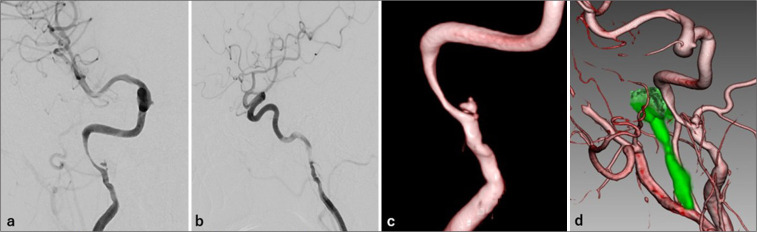

Case description: We report the case of a 45-year-old woman who presented with isolated right-sided glossopharyngeal nerve symptoms - specifically, ageusia and pharyngeal discomfort - along with mild posterior neck pain. Initial evaluation by otolaryngology failed to identify the etiology. Subsequent imaging at our hospital revealed a spontaneous dissection of the right internal carotid artery extending from the third cervical spinal cord level to the proximal petrous segment. Magnetic resonance angiography and digital subtraction angiography confirmed the diagnosis of ICAD. Conservative management with antiplatelet therapy (aspirin 100 mg/day) led to symptom improvement, and follow-up imaging after 180 days demonstrated near-complete resolution of the dissection.